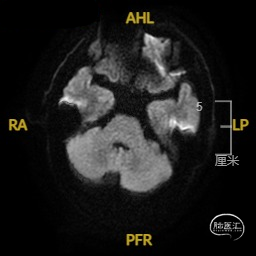

➢ 入院后头核磁检查

患者主因言语不利3天入院,头核磁提示右侧额、顶叶多发低灌注梗塞,脑血管造影提示右侧颈内动脉开口重度狭窄,为责任血管,另外患者前交通动脉、右侧后交通动脉开放不良,并且狭窄严重,考虑到高灌注风险,决定分期处理,一期小球囊扩张改善供血,二期支架成型。